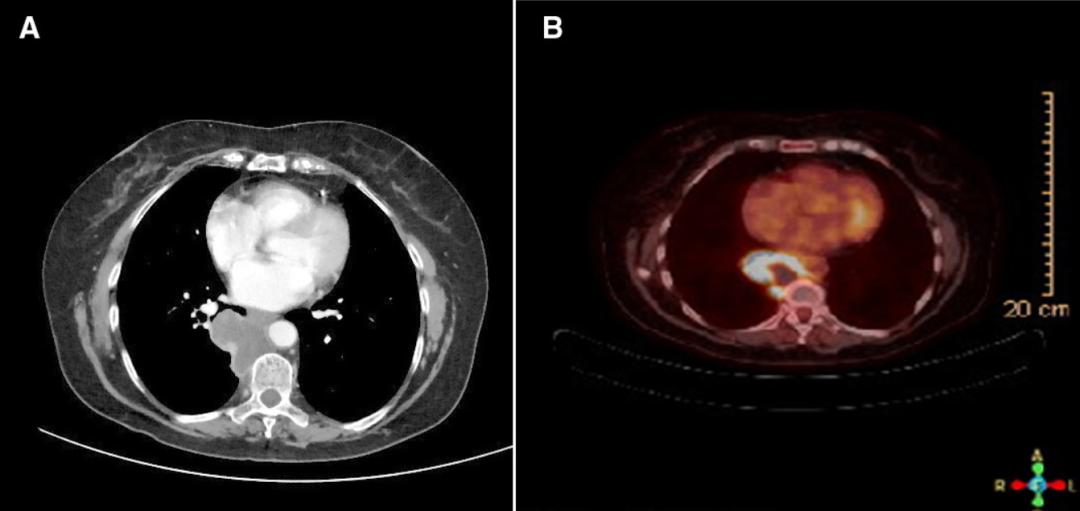

2020年6月复查影像学显示肿瘤对治疗有轻微反应(图2)。并且,患者最初的严重背痛症状在第一个疗程后完全消失。胸部肿瘤委员会再次讨论了患者的病例,考虑到影像学显示肺部肿块有严重坏死和患者背痛的完全缓解,决定进行手术切除。

图22020年6月25日,患者接受了右肺下叶切除术,并对T8和T9椎体进行了截骨术。患者实现了完全切除,边缘阴性(R0切除)。显微镜下,肿瘤标本中有98%的坏死,仅有少量残余鳞状细胞癌灶,手术边缘(-),肺门和纵隔淋巴结(-)(图3)。PET扫描显示,轻微活动的肺门淋巴结对治疗没有反应。术后,患者接受了强度调节放射治疗(IMRT,调强放疗),并继续派姆单抗治疗。